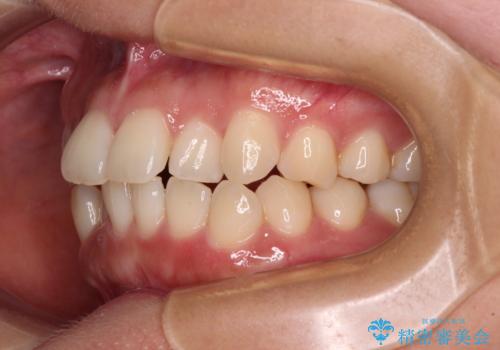

上下前歯のデコボコ ワイヤー装置で楽して改善

- 上下前歯のデコボコを気にして来院された患者様です。

ワイヤー矯正でもインビザラインでも、どの装置でも対応可能でしたが、安価で楽して素早く治療を終えたいとのことで、メタルブラケット装置による矯正治療を行うこととしました。

治療中は大きなトラブルもなく、予定の1年半でスムーズに治療を終えることができました。